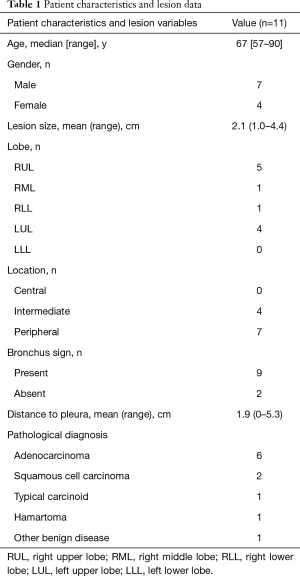

A total of eleven patients were enrolled between October 2013 and August 2017. The original target was 20 patients over 2 years; slow accrual prompted the decision to close the study before reaching this sample size goal. The patient characteristics and lesion information are summarized in Table 1. The details of each patient and diagnostic outcomes are listed in Table 2. There were seven male and four female patients with a median age of 67 years (range, 57–90 years). The mean size of pulmonary nodules on CT was 2.1 cm (median, 2.0 cm; range, 1.0–4.4 cm). Nine pulmonary nodules (82%) had a positive CT bronchus sign. Seven pulmonary nodules (64%) were located in the peripheral third lung field. The mean pleural surface-to-pulmonary nodule distance was 1.9 cm (median, 1.9cm; range, 0-5.3 cm). Representative CT images of the pulmonary nodules are shown in Figure 2. Seven cases underwent conventional bronchoscopy as the first procedure. Biopsy tools used for each case are shown in Table S1. Ten out of eleven patients underwent surgery for diagnosis and treatment. One patient (case #4) was surveilled by imaging alone, with a total of three CT scans over two years; the nodule was clinically diagnosed as benign due to diminishing size.

Full table

Full table